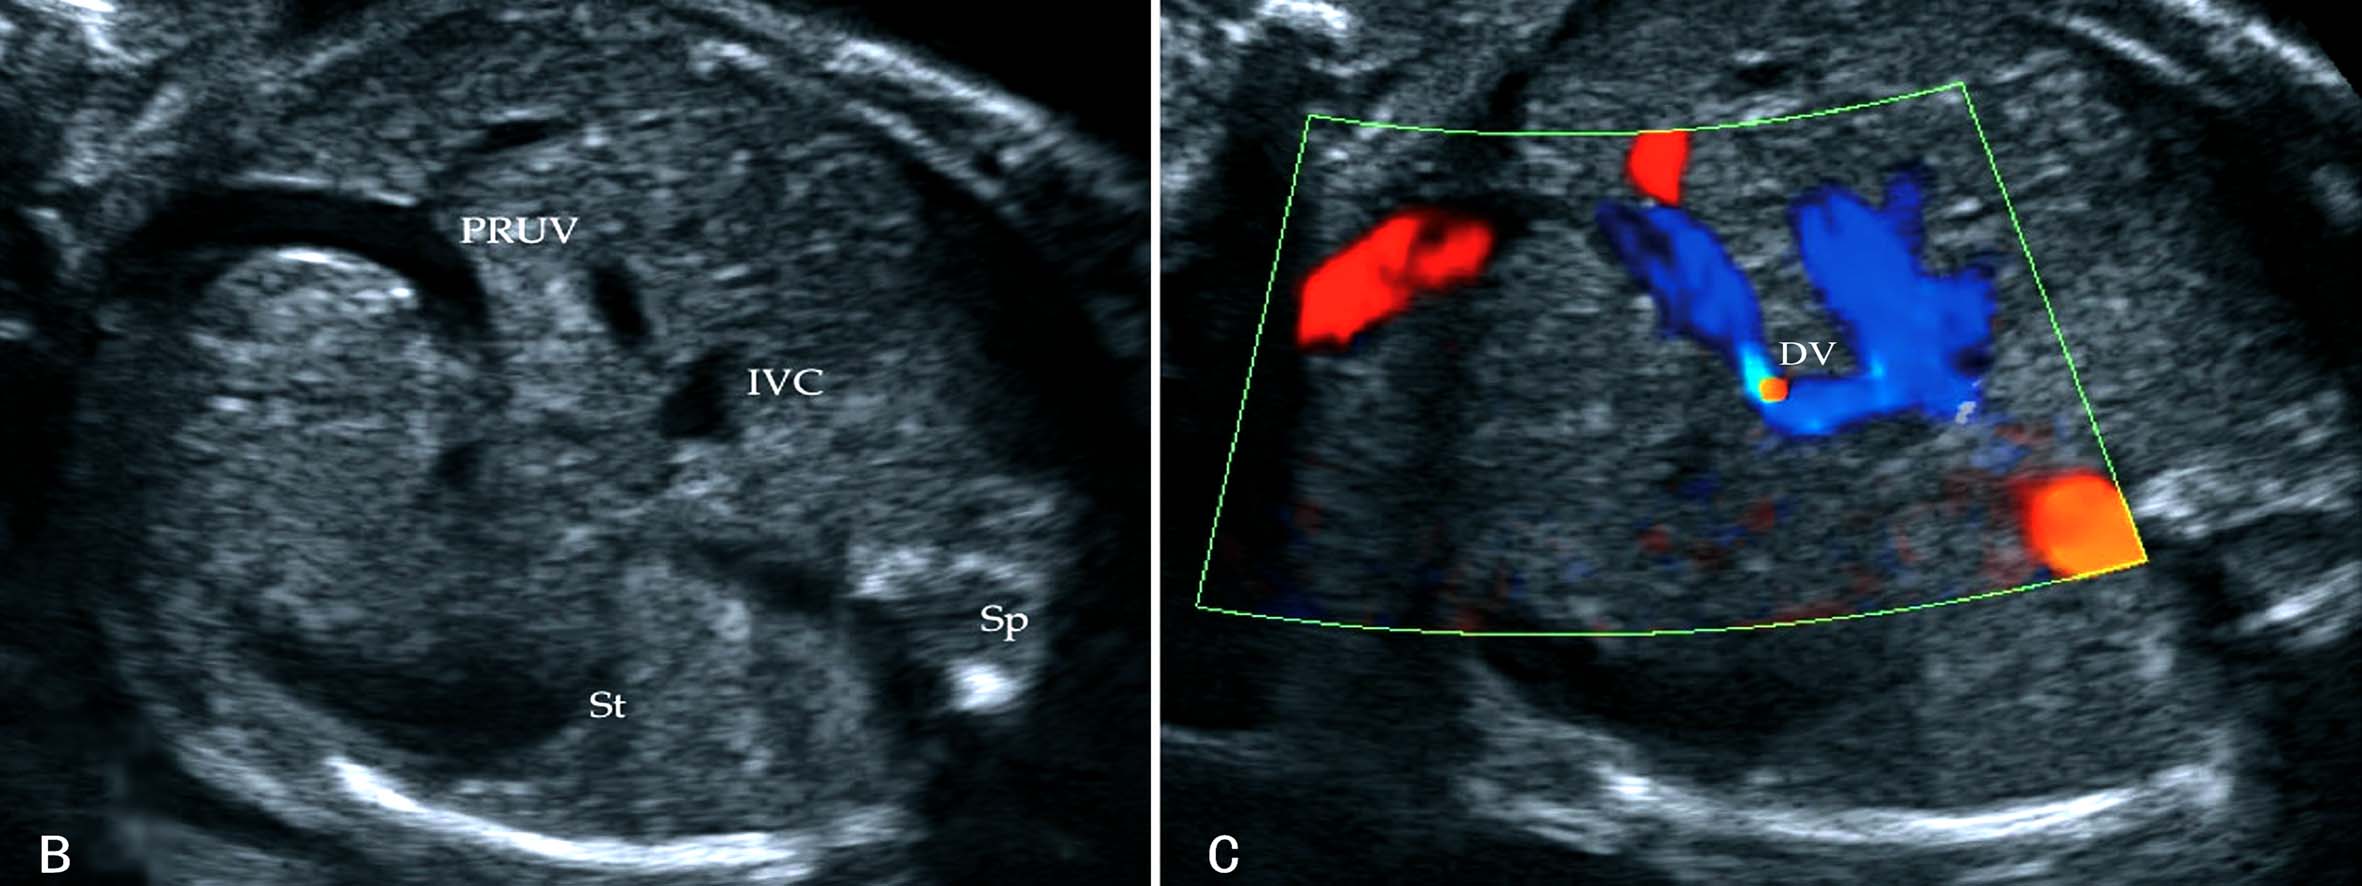

胎儿腹部横切面显示胃泡和脐静脉以后视察胆囊的位置可以确定脐静脉走行。正常脐静脉穿过脐轮后走行于胆囊的左侧,在胆囊与胃腔之间可以显示脐静脉的回声(图8A);如果在胆囊右侧显示脐静脉回声即可明确右脐静脉的诊断((图8B));肝内型持续性右脐静脉进入肝脏后PRUV需要转向左侧与静脉导管连接(图9)。连续追踪扫查如果显示脐静脉周围或一侧无肝脏实质,则提示为肝外型持续性右脐静脉。一般认为,后者常合并其他部位的发育异常,并可以合并染色体异常。

图8 正常脐静脉与持续性右脐静脉声像图比较

图11-54 持续性右脐静脉声像图